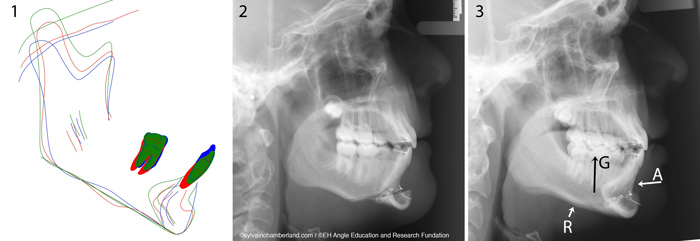

Génioplastie fonctionnelle chez le patient en croissance

Keynote: Genioplastie fonctionnelle chez le patient en croissance Voir le document Angle Orthodontist online early Voici un article concernant un projet de recherche sur le remodelage osseux après une génioplastie fonctionnelle selon l’âge d&rs [...]

Titre de la conférence: Functional Genioplasty in Growing Patients. Un article décrivant ce projet de recherche a été soumis au journal Angle Orthodontists et a été accepté pour publication. Il sera bientôt disponible. . . .